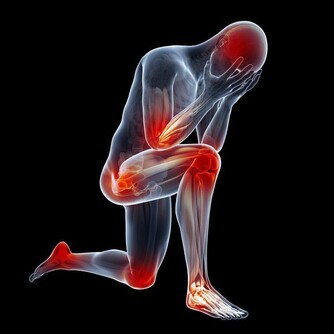

絕經後由於雌激素突然和明顯的缺乏會引起一些不適,有人在絕經前期就可發生。常表現為心情和情緒的變化,煩躁、易激動、失眠,焦慮,陣發性臉潮紅、潮熱、出汗,皮膚瘙癢、有時皮膚還有蟻爬的感覺,並且皮膚失去彈性,皺紋增多,肌肉逐漸鬆弛,時有疼痛,易疲勞或乏力、頭疼、頭暈和血壓不穩等。

這些症狀叫做更年期綜合徵。

2.遠期症狀

(2)骨質疏鬆

(4)心血管疾病